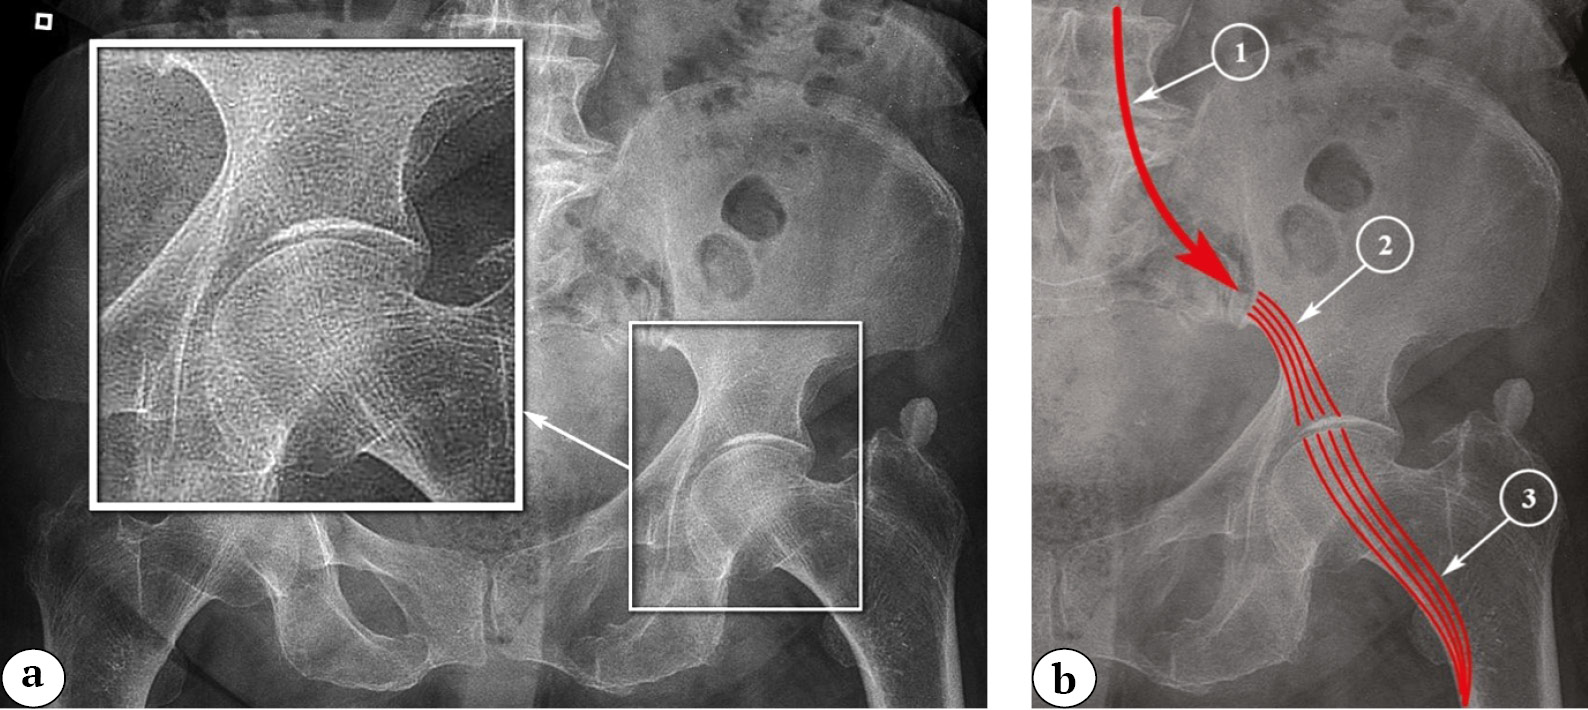

Horizontal fractures form the second major group of fractures that are relatively stable and typically do not require fixation. In our view, these fractures result from incomplete symphyseal disruption. The symphysis is surrounded by ligaments in the form of a cuff, where the upper and lower ligaments are the most robust, while the anterior and posterior ones are the weakest. Deforming forces on the front part of the pelvis lead to the disruption of the anterior symphyseal ligament, continuing to act on the base of the pubic bone in the form of horizontally oriented fractures (Fig. 5). Both the powerful upper and lower symphyseal ligaments can be damaged in the process (Fig. 6).

Fig. 5. Incomplete symphysis rupture with horizontal fracture of the pubic bone base: a — 3D-CT image reconstruction; b — 2D-CT image of incomplete symphysis rupture and the direction of the traumatic force; c — 2D-CT reconstruction, the arrow indicates symphysis gap widening; d — 2D-CT image reconstruction in the sagittal view of the pelvis, the arrows indicate the fracture line extending into the symphysis

Fig. 6. Pelvis X-ray in the AP view. The arrows indicate the rupture of the superior ligament of the symphysis and partial widening of the symphysis, horizontal fracture of the base of the pubic bone (a); 2D-CT image reconstruction of the pelvis in the sagittal view. The arrows mark the displacement of the fragments (b)

Thus, in addition to the well-known complete disruption of the symphysis, it is necessary to distinguish partial disruption of the symphysis in the presence of a horizontal fracture of the pubic bone’s base. As a result, we propose a straightforward classification of pubic symphysis disruptions:

– incomplete disruption pubic symphysis (with or without displacement);

– complete disruption pubic symphysis (with or without displacement).